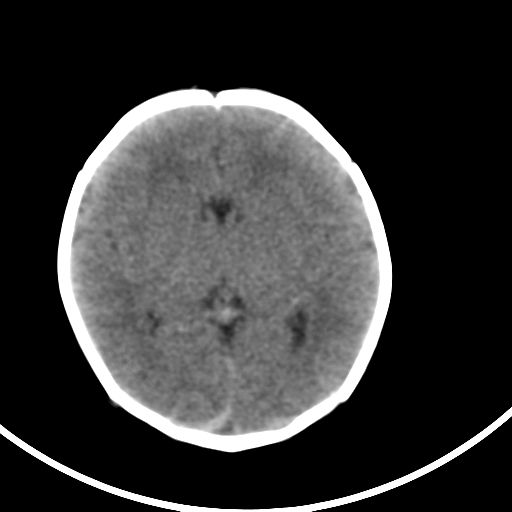

新生儿3天,超过预产期5天剖宫产,有缺氧病史,具体评分不详,现反应差,肌张力低,前囟平,原始反射存在,无苦闹等。

kaolv小脑幕,后纵裂区蛛网膜下腔出血;轻度脑肿胀

矢状窦旁征——支持蛛网膜下腔出血

sah。